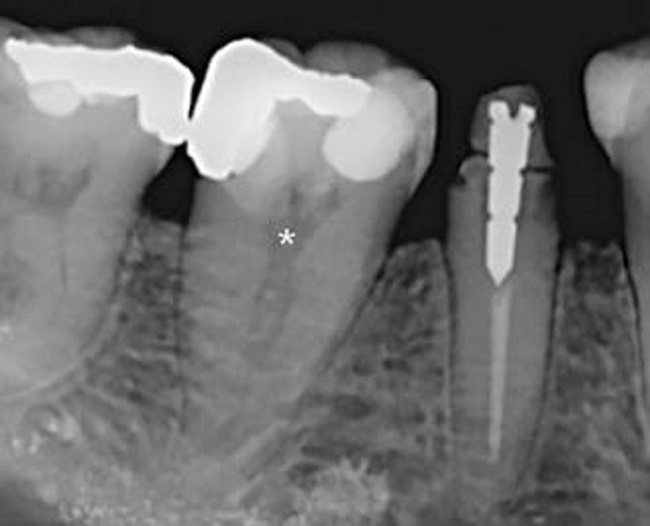

Paciente mujer de 48 años de edad sin antecedentes médicos de mención, fue derivada al Área de Endodoncia de la Clínica Odontológica Docente Asistencial (C.O.D.A.) de la Facultad de Odontología de la Universidad de La Frontera (Temuco, Chile) para realizar tratamiento del primer molar mandibular izquierdo permanente (diente 46), indicado este procedimiento por una posterior rehabilitación protésica. Luego de realizadas las pruebas clínicas usuales, se llegó al diagnóstico de “pulpitis irreversible asintomática con tejidos apicales normales”. El examen radiográfico preoperatorio demostró la presencia de restauraciones profundas, una cámara pulpar levemente retraída y el hallazgo inusual de un canal centrado en una única raíz (Figura 1), de tipo I según la clasificación de Vertucci 13. Informada la paciente de esta situación, consentido el procedimiento, y procediendo al tratamiento endodóntico no quirúrgico de rutina, se realizó el acceso convencional a la cámara pulpar con fresas específicas e instrumental rotatorio. La trepanación permitió la confirmación macroscópica de un único gran canal localizado en el centro de la cámara pulpar, el cual fue preparado quimiomecánicamente siguiendo los protocolos estándar de la institución. Debido a la "particularidad" de la anatomía canalicular, y para evaluar potenciales presencias de canales accesorios o enmascaramientos morfológicos que pudieran condicionar el éxito del procedimiento, se consideró realizar CBCT antes de continuar con el tratamiento endodóntico en una sesión posterior.